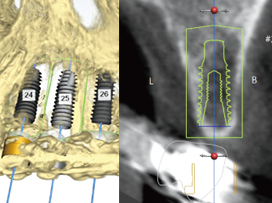

• 3D Diagnosis via CT Scan

Using 3D data from CT imaging and dental models, we perform a comprehensive and precise diagnosis that considers bone, gingiva, and nerve anatomy.

• Computer-Based Surgical Planning

We perform a virtual simulation surgery on the computer to determine the precise placement position, then fabricate a custom surgical guide for accurate execution.

• Detailed analysis of bone tissue and nerve location

• Precise selection of optimal implant position